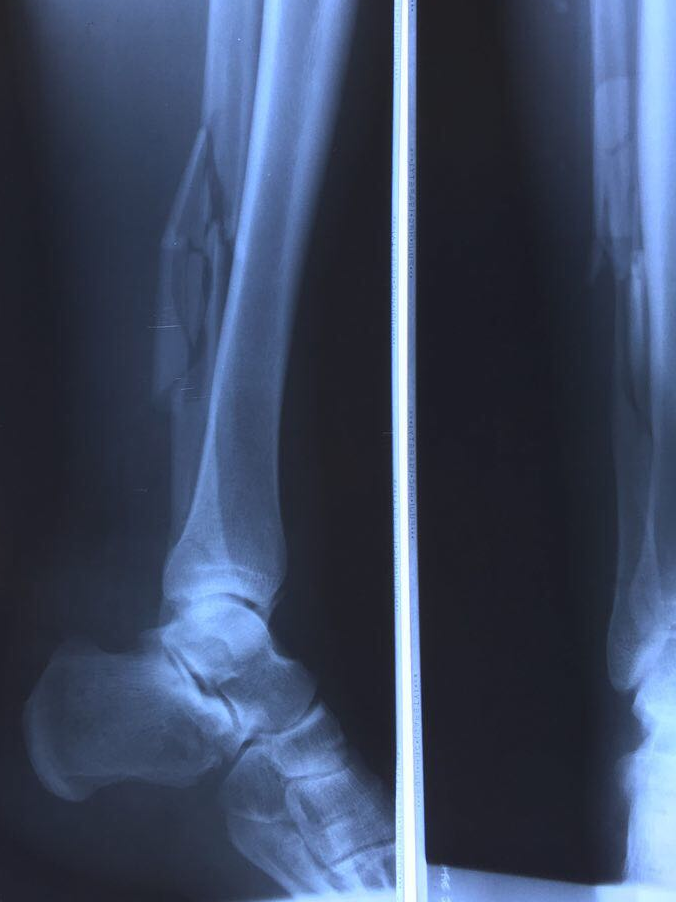

рентген сразу после аварии

Эскизы прикрепленных изображений

Судебная медицина - Прикрепленное изображение

1. перелом внутренней и внешней лодыжки правой голени

2. отсутствует разрыв связок (межберцового синдесмоза)- они не повреждены

3. открытый перелом малой берцовой кости

Перелом собрали- даже пластину ставить не потребовалось на малоберцовую кость. Так что без каких либо металлических штук нога заживает- и это замечательно. Лодыжку держат спицы.